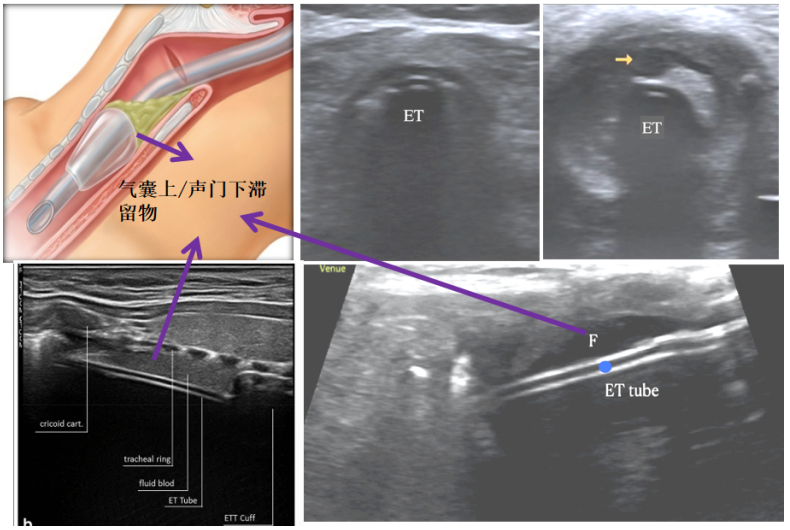

6. 声门下/气囊上滞留物监测

通常我们会用声门下吸引(SSD)或气流冲击法清除气囊上的滞留物,同时还可以利用超声监测清除效果。将超声/血管探头置于锁骨下区域,通过横切和纵切进行观察,当气管插管进入气道后,理论上来讲,气管插管与气道内壁之间有空气,由于有空气遮挡,我们不能看到完整的双轨征/子弹征。但如果在超声下看到了一根完整的气管插管,或双轨征,或一些高回声的液体,都提示气囊上滞留物过多,需要积极引流或清除。图20左下为气管插管过程中气道损伤患者,插管后通过气道超声发现双轨征,且在气管插管与气道内壁之间有很多匀质的低回声区,这是插管过程中损伤所致出血集聚在气囊上,也是典型的表现。

图片

图20  超声监测声门下/气囊上滞留物